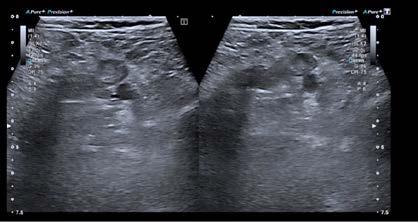

Se realizó una tomografía computarizada (TC) con contraste de forma emergente, que mostró una disección aórtica iatrogénica tipo A focal de origen en la zona 0 del cayado con extensión al tronco braquiocefálico derecho (1) sin afectar al resto de troncos supra-aórticos, cayado o aorta descendente (Figuras 1 y 2); además del hematoma

Figuras 1 y 2: Prótesis aórtica migrada y disección aórtica focal tipo A, de origen en la curvatura menor del arco aórtico (zona 0) hasta la bifurcación de la arteria braquiocefálica derecha; sin afectación de del resto de troncos supra-aórticos, del resto del cayado aórtico o de la aorta descendente.